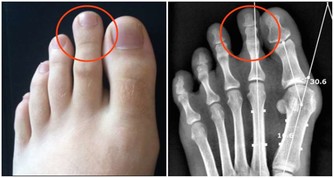

肺與大腸相表裡,肺氣虛也會影響大腸的蠕動功能,造成便秘。